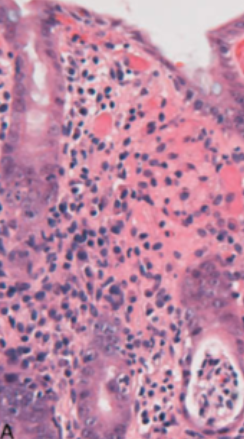

55yo male presents with persistent, vague epigastric pain for many months. Associated with this is nausea and weight loss. He has a history of H. pylori infection

Stomach cancer (adenocarcinoma shown)